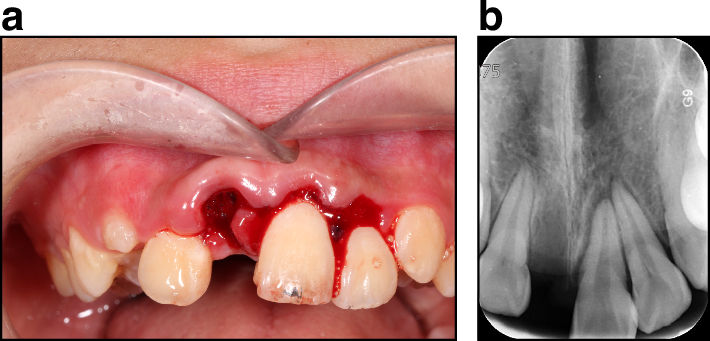

Concussion (Tooth #12, by FDI notation system), a subluxation (Tooth #22), extrusive luxation (Tooth #21), and avulsion (Tooth #11). a Clinical exam. b Radiograph exam